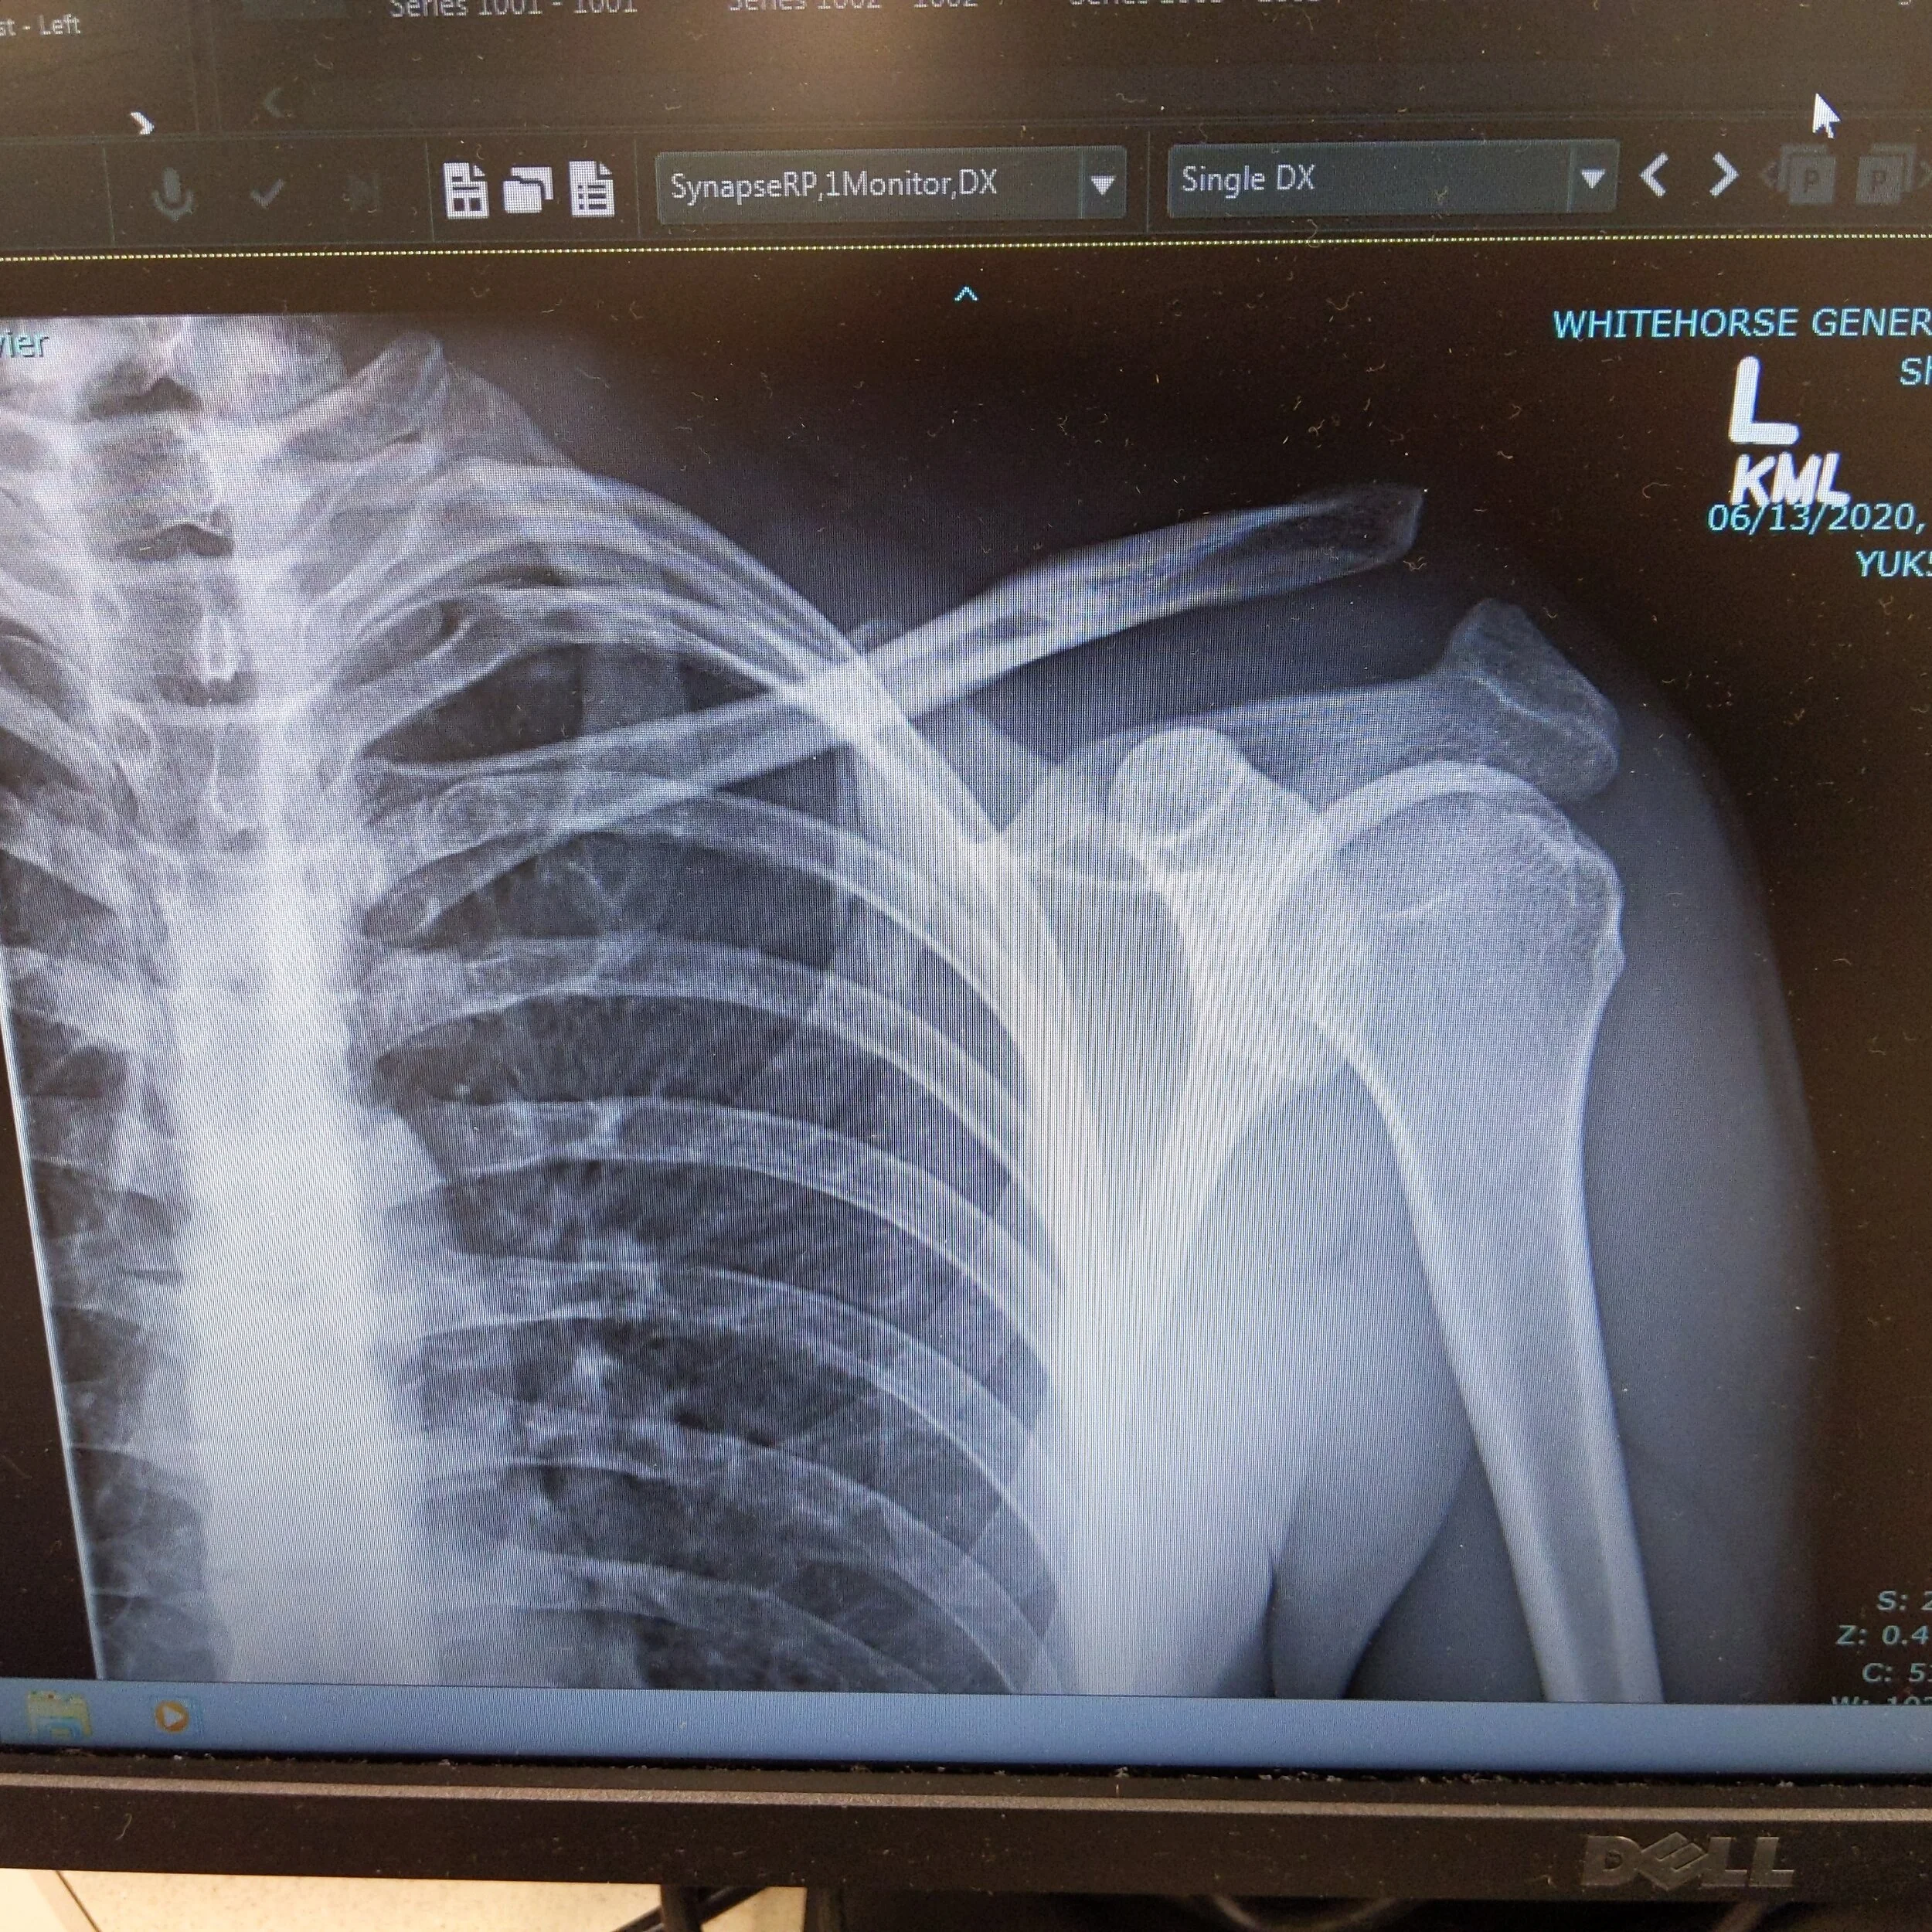

I made a mistake and bit off more than I could chew.  I tried dropping off the first big feature on the Gnar Wall trail going way too slow and landed myself into an ambulance with a separated shoulder and some banged up ribs.

The ending of this story is that I now have a massive and permanent deformity on my left shoulder and some broken ideas about mountain biking.  It’s hard to get stoked about a sport when it feels like it robbed you of a summer. Being unable to play trumpet, rock climb or hike was not a trade off I would have ever made.  We’ll have to wait and see if this winter makes me forget enough to start sending it again ;-).